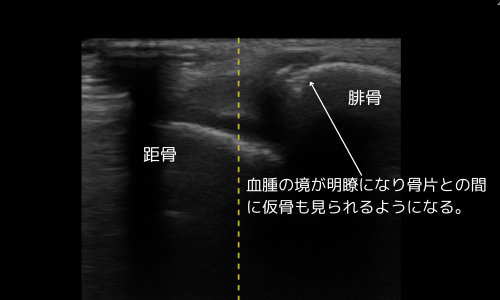

10月7日(受傷約2週間)

- 血腫境界明瞭、仮骨形成を確認

- 腫脹の軽減、圧痛一部残存